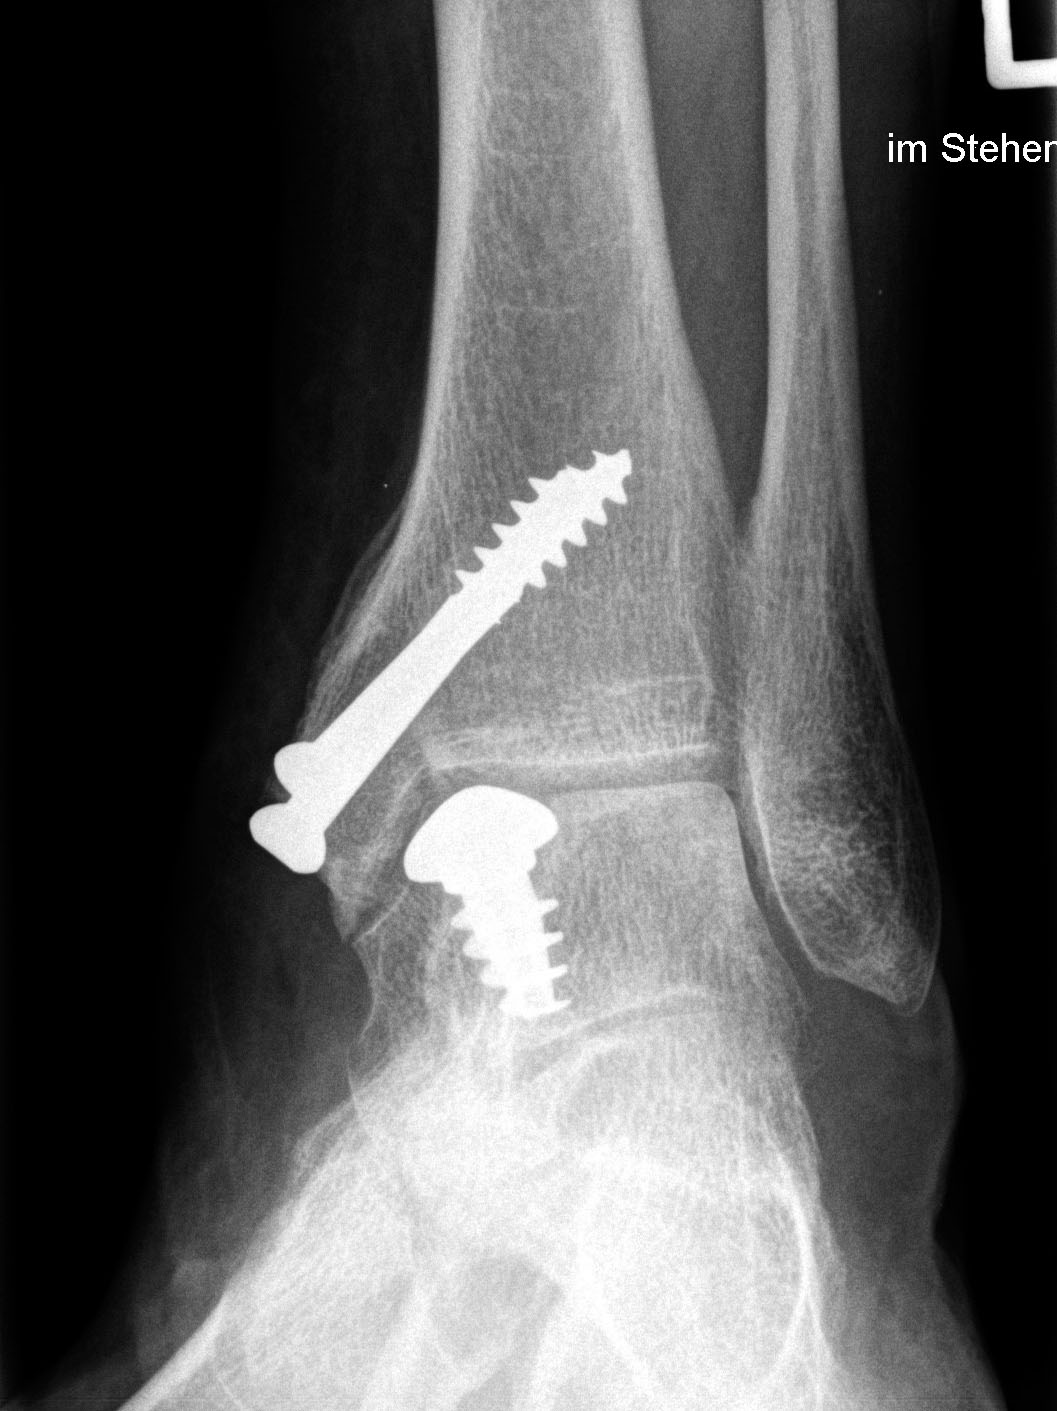

Eine vorausgehende Arthroskopie ist zu empfehlen. Zum Einbringen des Implantates ist eine Osteotomie des medialen Malleolus erforderlich.

Zum Lesen der Bildbeschreibung und zur Vollansicht bitte die Bilder anklicken. Bilder: Christoph Becher.

Abschließend erfolgt die Osteosynthese des medialen Malleolus und der schichtweise Wundverschluss. Anschließend Anlegen eines sterilen Wundverbandes sowie Ruhigstellung in einer Gipslonguette in Neutralstellung.

CAVE: Bei der postoperativen Röntgenkontrolle muss bedacht werden, dass die Knorpelschicht nicht abgebildet ist. Da das Implantat bei einer korrekten Positionierung unterhalb des Knorpelniveaus die knöcherne Fläche dennoch etwas überragt, kann dies zu einer Fehlinterpretation führen, dass das Implantat übersteht.

Zum Lesen der Bildbeschreibung und zur Vollansicht bitte die Bilder anklicken. Bilder: Sarah Ettinger.